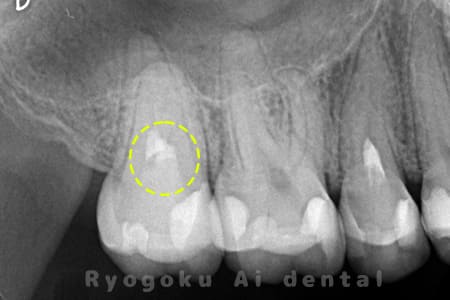

Case08

右下に違和感があるとのこでご来院。レントゲンでも神経に達する虫歯があり、神経の保存を行う断髄治療について説明し、同意を得て行いました。特に知覚過敏症状もなく、神経の反応も良好なため、今後は定期検診にて経過を追っていくこととなりました。

<リスク・副作用>

術後は痛み、腫れ、痺れなどの副作用が生じる場合があります。症状が再発する可能性があります。その場合は抜髄する必要があります。